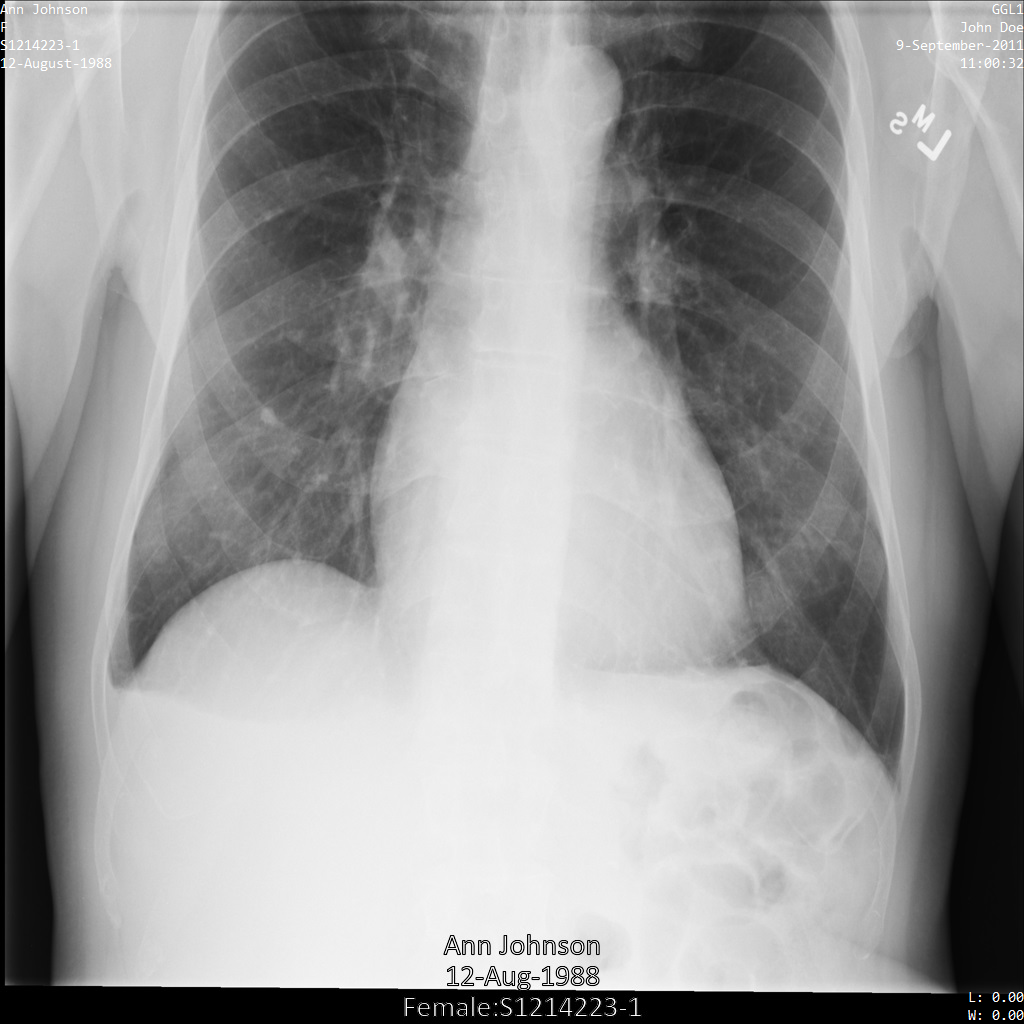

以下各節提供範例,說明如何使用各種方法去識別 DICOM 資料。每個樣本都會提供去識別化圖片的輸出內容。每個範例都會使用下列原始圖片做為輸入內容:

您可以比較各項去識別化作業的輸出圖片與原始圖片,瞭解作業效果。

將圖片提交給 Cloud Healthcare API 後,圖片會如下所示。雖然圖片頂端角落顯示的中繼資料已遭塗銷,但圖片底部的內建受保護健康資訊 (PHI) 仍存在。如要一併移除內建文字,請參閱「從圖片中遮蓋內建文字」。